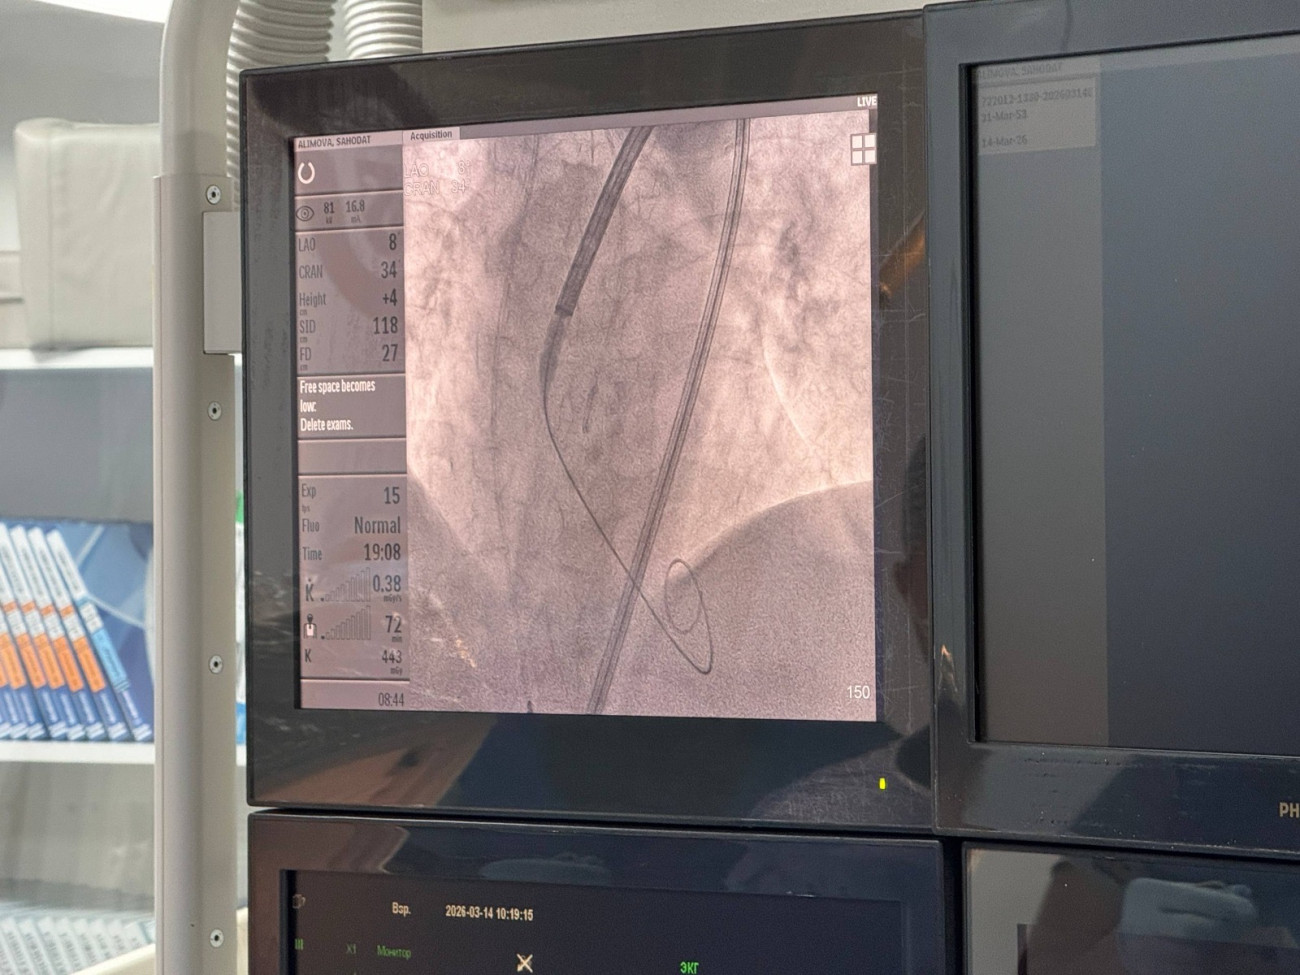

Ош мамлекеттик университетинин медициналык клиникасында 72 жаштагы бейтаптын жүрөгүнө заманбап TAVI операциясы – хирургиялык чоң кесүүсүз транскатетердик аорталык клапанды имплантациялоо ыкмасы ийгиликтүү жасалды. Бул операция клиникада биринчи жолу колдонулду.

Бул ыкмада салттуу операциядагыдай чоң хирургиялык кесүү жасалбайт. Буттагы кан тамыр аркылуу ичке катетер киргизилип, жүрөккө жаңы аорталык клапан орнотулат. Операция болжол менен бир жарым саатка созулуп, ийгиликтүү аяктады. Клиниканын кардиохирургу Заир Сыргаевдин айтымында, мындай операциянын негизги артыкчылыгы бейтаптын тез калыбына келүүсү болуп саналат.